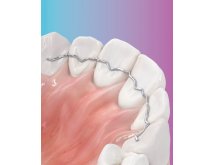

Édition entièrement refondue et riche en nouvelles illustrations, Ursula Wirtz présente les principaux appareils orthodontiques amovibles.

En tant que manuel de travail et d'études, cet ouvrage de référence pour la technique amovible en orthodontie renferme de nombreuses illustrations et constitue une aide précieuse, aussi bien pour le prothésiste dentaire que pour l'orthodontiste.

L'o-atlas II indique de manière précise et concise les aspects à prendre en compte lors de la fabrication d'un appareil orthodontique. Cette édition en français se distingue par sa conception moderne et attrayante.

Plus de 1000 illustrations.